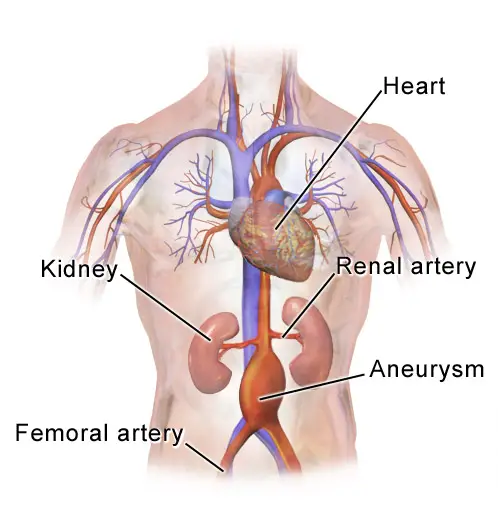

Abdominal Aortic Aneurysm

Abdominal aortic aneurysm (AAA) is an aneurysm of the abdominal aorta.

Abdominal aortic aneurysm typically develops above the aortic bifurcation but below the renal arteries.

Abdominal aortic aneurysm (AAA) is typically associated with hypertension and atherosclerosis.

Abdominal aortic aneurysm (AAA) typically presents with a triad of:

- Flank pain

- Pulsating abdominal mass

- Hypotension

Symptoms of abdominal aortic aneurysm include an abdomen lump that pulses initially and enlarges over time.

Complications of abdominal aortic aneurysm (AAA) include:

- Rupture, especially when the diameter is greater than 5 cm

- Compression of nearby structures (such as the ureter)

- Thrombosis

- Embolism